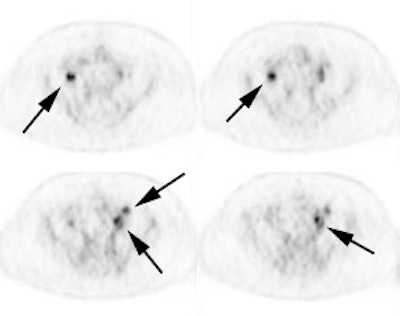

Initial staging for extrahepatic metastases: The patient below underwent FDG PET imaging to assess for extrahepatic metastatic disease prior to definitive surgical intervention. The PET exam demonstrates uptake within two hepatic metastases (black arrows on PET scan and yellow arrows on CT images) and in the patients primary colon cancer (blue arrow on PET scan and white arrow on CT image). No other sites of abnormal tracer uptake were identified which supports surgical intervention in this case. |

|